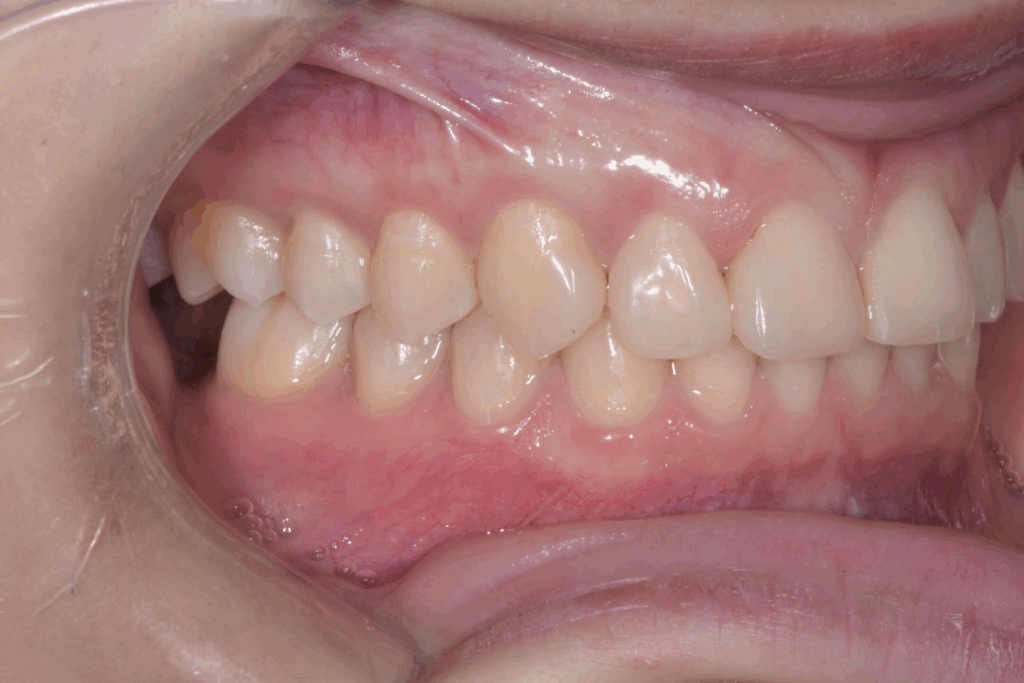

La prima fase del trattamento è stata un’analisi approfondita. Durante il check-up, abbiamo confermato la diagnosi di agenesia dei secondi molari permanenti inferiori, una condizione congenita che lascia spazi vuoti nell’arcata. Abbiamo inoltre rilevato che gli incisivi superiori erano di dimensioni ridotte rispetto al resto dei denti e che la paziente presentava un morso profondo, con gli incisivi superiori che coprivano eccessivamente quelli inferiori. Questa valutazione completa ci ha permesso di creare un piano di trattamento personalizzato e preciso, tenendo conto di tutte le problematiche presenti.

Per affrontare le sfide del caso, abbiamo optato per l’utilizzo di allineatori trasparenti. Questo tipo di trattamento è stato scelto per la sua efficacia nel muovere i denti in modo preciso e graduale, ma anche per la sua discrezione, fondamentale per una paziente in età scolare. Il piano di trattamento ha previsto una serie di allineatori personalizzati, che la paziente doveva sostituire con il passare delle settimane.

- Chiusura degli spazi: gli allineatori sono stati programmati per spostare i denti posteriori e chiudere gli spazi vuoti lasciati dall’agenesia dei settimi, evitando la necessità di impianti o ponti.

- Correzione della verticalità: il trattamento ha lavorato per estrusione e intrusione selettiva di alcuni denti, al fine di correggere il morso profondo e ristabilire una corretta occlusione.